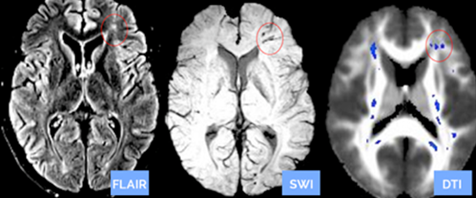

DTI can measure and evaluate small and subtle brain injuries by comparing a patient’s scan to a control group of normal subject DTI scans. This quantitative process helps to diagnose the specifically injured areas of the brain that can help physicians confirm the presence of nerve damage. A patient undergoing a quantitative DTI scan has a similar experience to a patient having a regular brain MRI scan, but the DTI results can reveal much more. As seen in the image below, the blue spots in the DTI brain scan on the right are nerve damage not seen in the two other standard scans of the same brain.